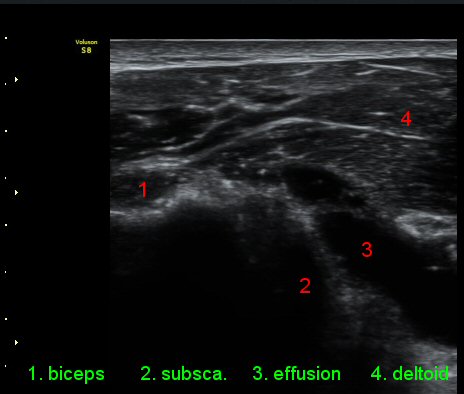

ÀÌµÎ¹Ú±Ù°Ç È¾´Ü¸é°Ë»ç¿¡¼­ °ÇÁÖÀ§¿¡ ¼Ò·®ÀÇ ¼ö¾×Àú·ù¿Í Á¡¾×³¶³» ¾×Àú·ù°¡ °üÂûµÈ´Ù(»çÁø 1, 2).